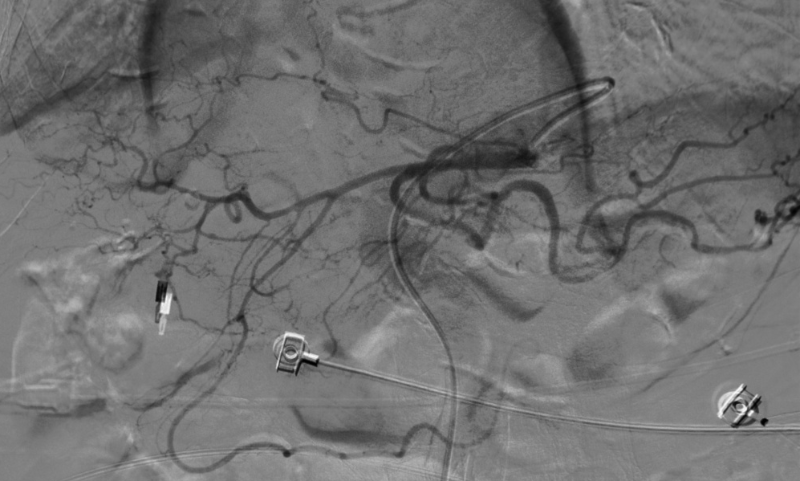

術中造影顯示胸腹主動脈呈現2個S型彎曲,RH造影導管插入腹腔干非常困難,無法找到腹腔干。

更換造影導管及反復嘗試后,導管進入腹腔干動脈。